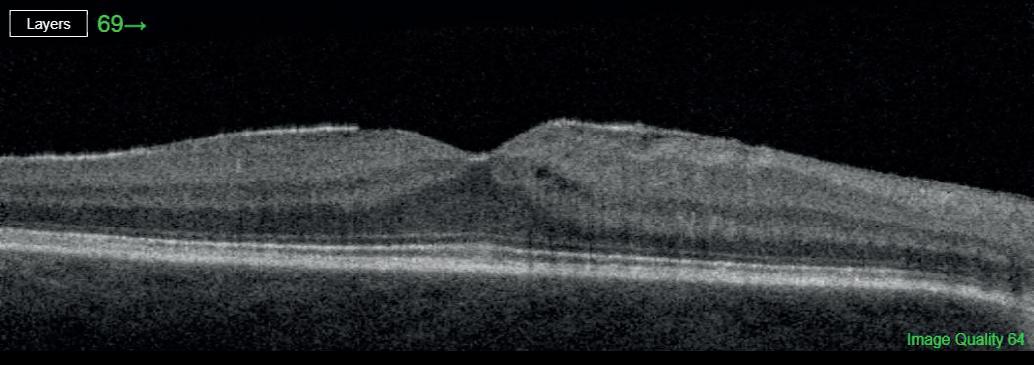

“For example, somebody who is suffering with diabetic macular oedema can receive very effective treatment with an injection of anti-VEGF [vascular endothelial growth factor] agent. To be able to start the treatment in England, according to NICE guidelines, you have to

have a central retinal thickness of at least 400μm. However, there is evidence that macular thickness is smallest in Black people, followed by Asian people, when compared with Caucasians. That means Black people are already disadvantaged and would require a much greater volume of macular fluid before being able to start treatment. That is a racial disparity in itself.”